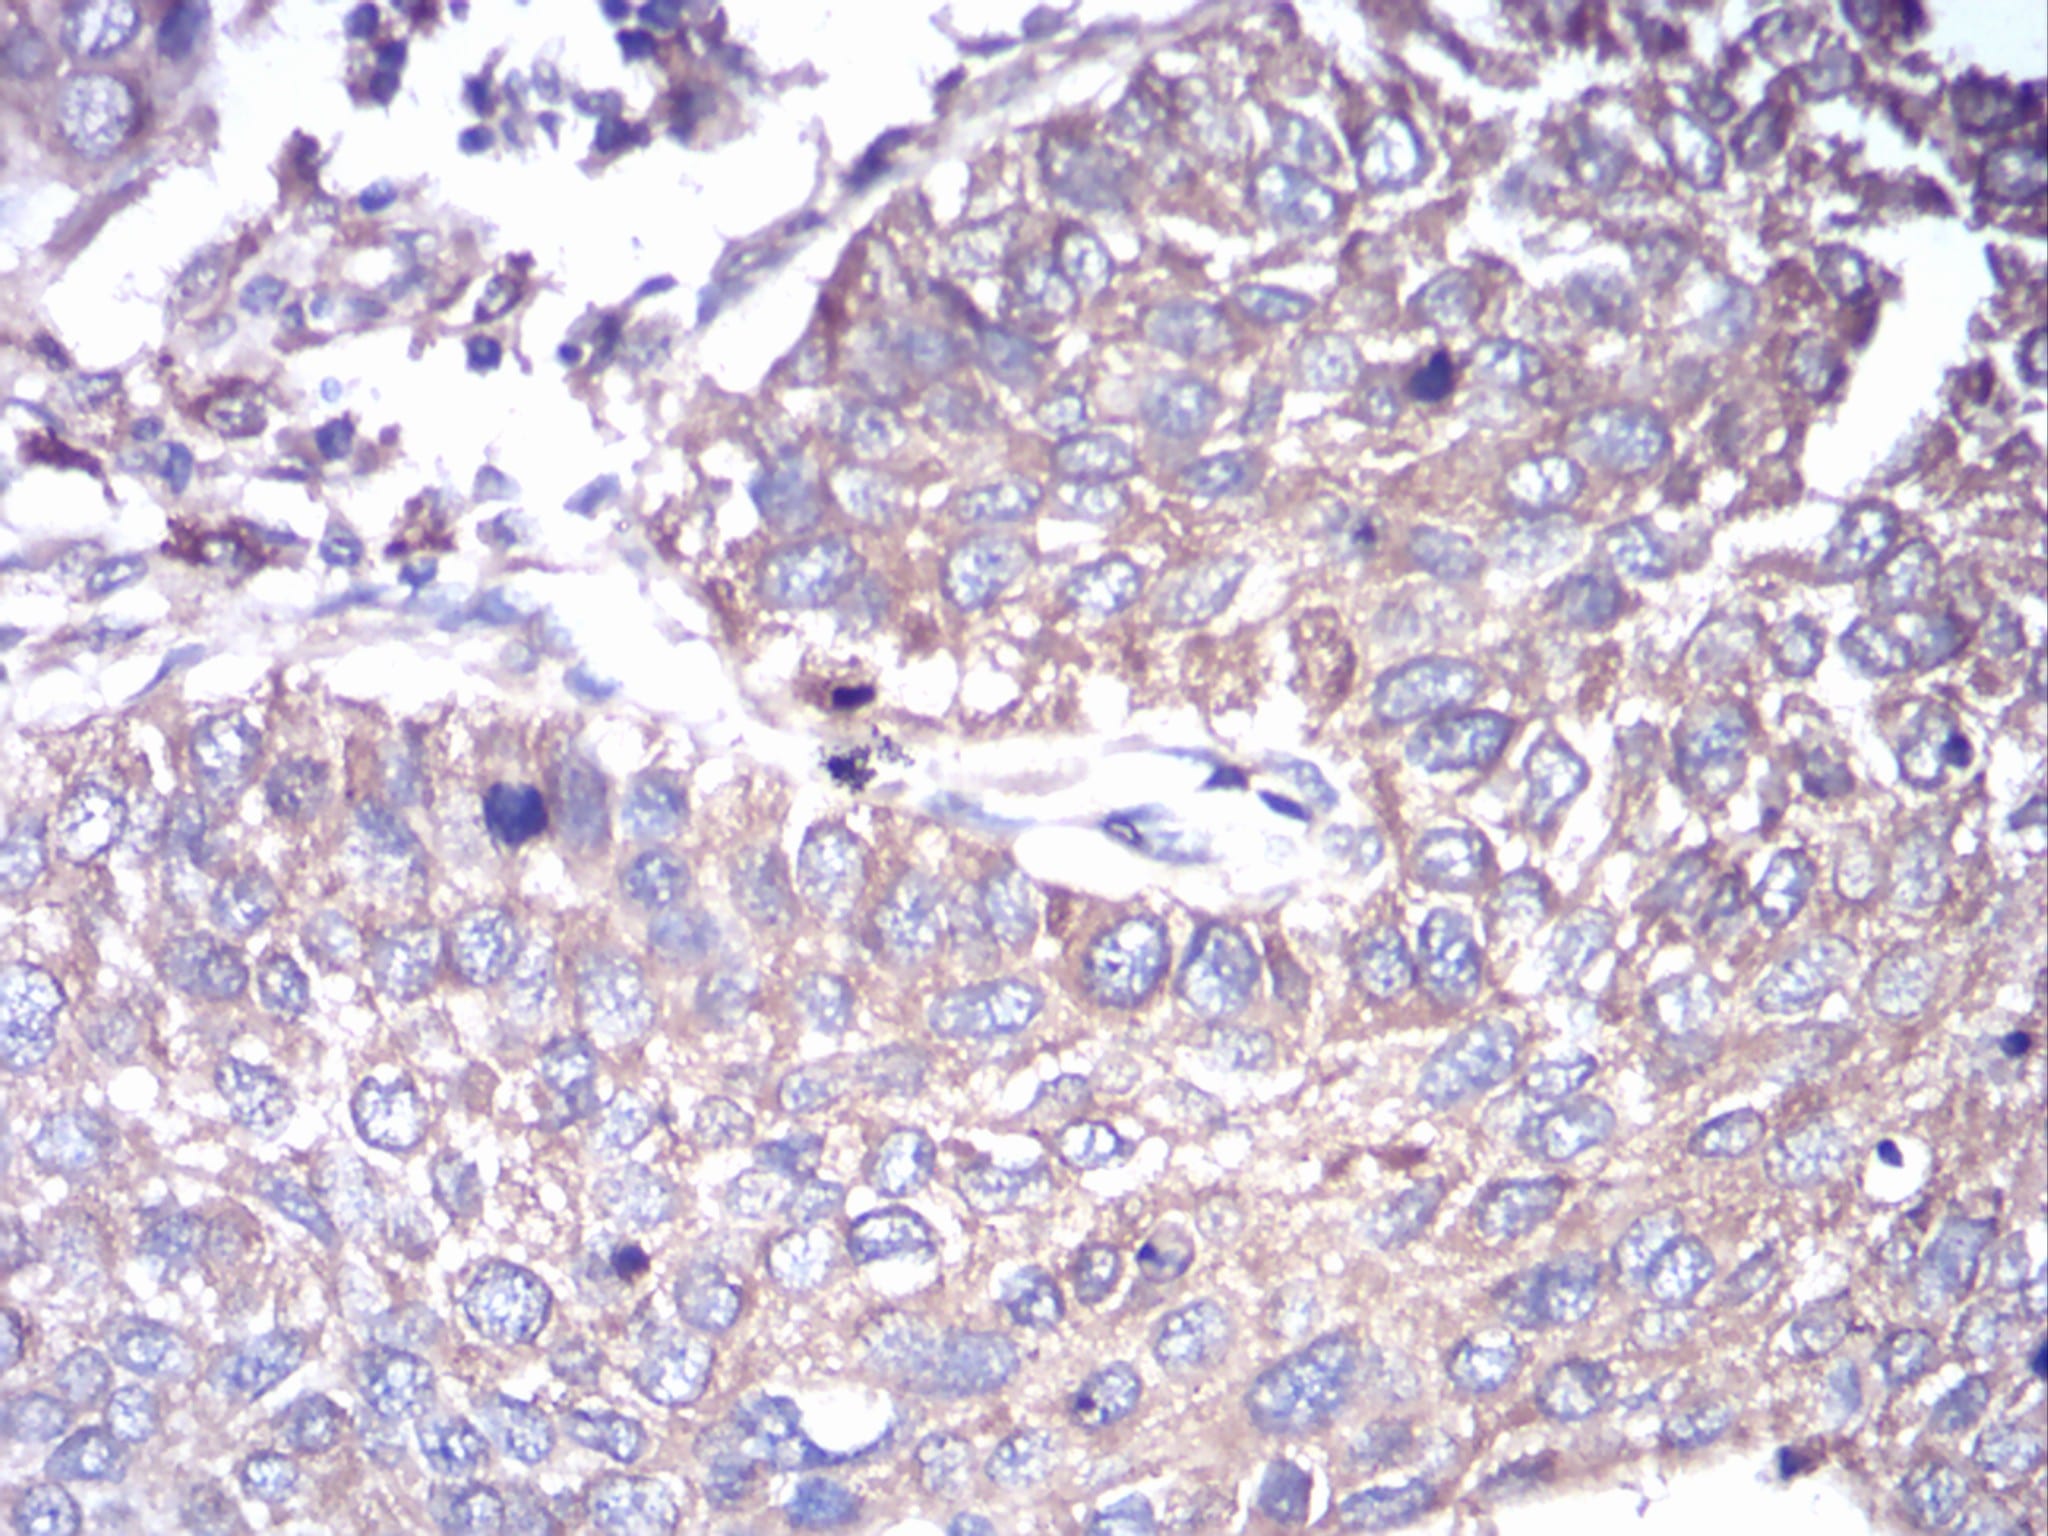

IHC 1/200 - 1/1000 Human,Mouse,Rat